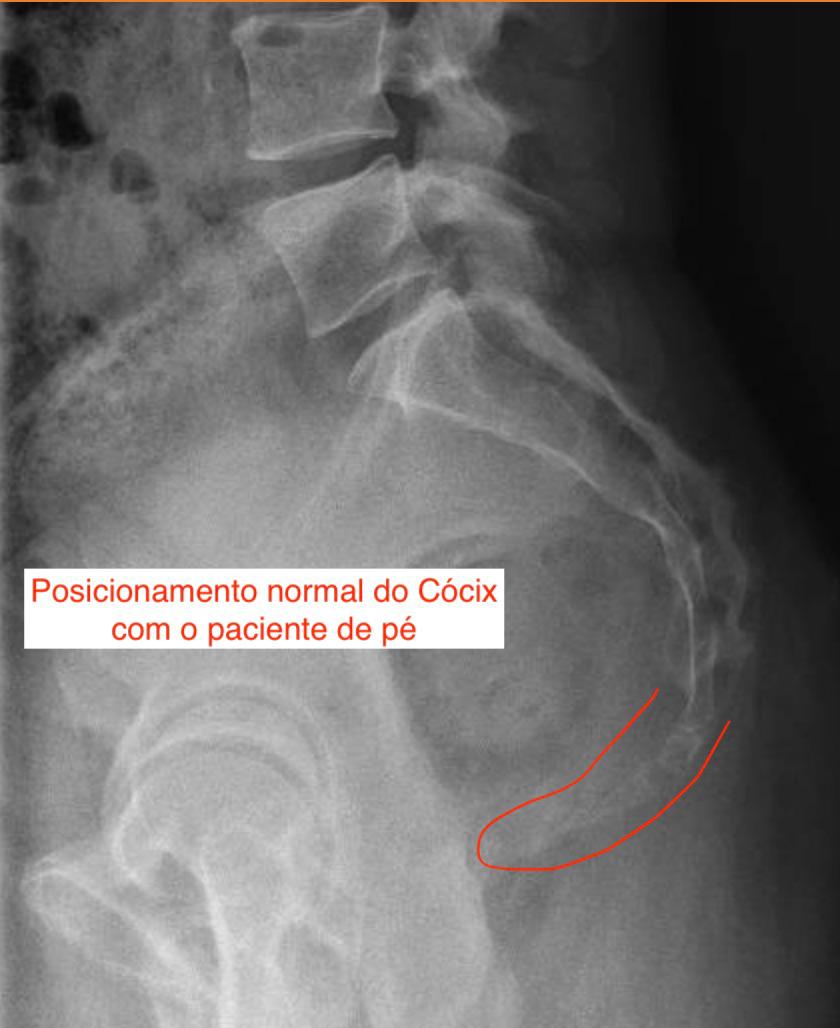

O exame clínico costuma ser o primeiro passo, mas em alguns casos, a fratura não aparece em radiografias simples. Nestes casos, um raio-x dinâmico pode ser essencial: esse exame é feito com o paciente em posições específicas, forçando a movimentação do cóccix para revelar instabilidades no osso.

Imagem de raio-x com a paciente em pé em que não é possível detectar a mobilidade do cóccix

Durante a consulta, suspeitamos de fratura e solicitamos um raio-x dinâmico. O exame revelou um deslocamento do fragmento do cóccix, confirmando a fratura oculta.